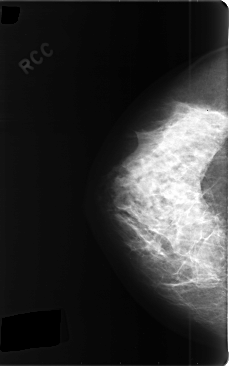

C_0358_1.RIGHT_CC

RIGHT_CC LINES 4752 PIXELS_PER_LINE 2976 BITS_PER_PIXEL 12 RESOLUTION 50 NON_OVERLAY